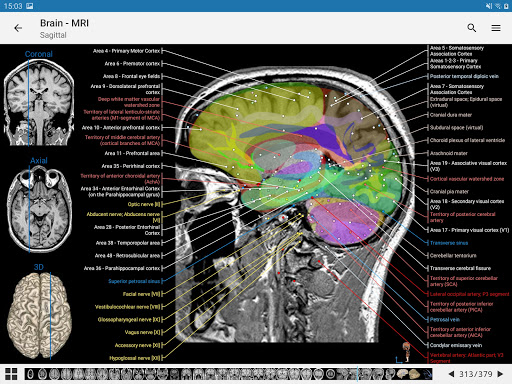

e-Anatomy tiene más de 26 000 imágenes que contienen series de imágenes en vistas axiales, coronales y sagitales, así como radiografías, angiografías, imágenes de disección, gráficos anatómicos e ilustraciones. Todas las imágenes médicas fueron etiquetadas cuidadosamente, más de 967 000 etiquetas disponibles en 12 idiomas, incluida la Terminologia Anatomica latina.

- Toque las etiquetas para mostrar las estructuras anatómicas

- Seleccione las etiquetas anatómicas por categoría

- Localice fácilmente las estructuras anatómicas gracias a la búsqueda de índice